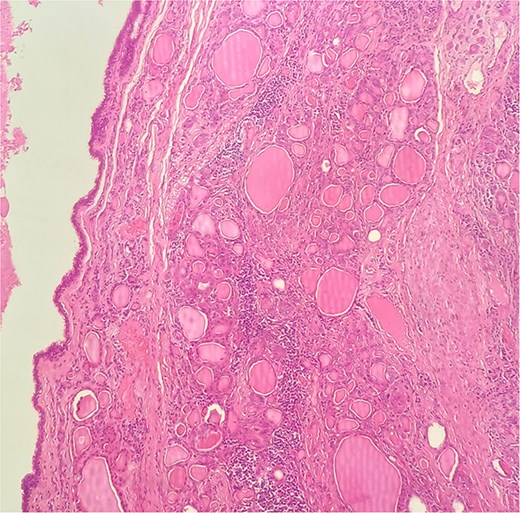

A 47-year-old woman with unremarkable medical history, presented with a 2 months history of neck mass along the midline. Physical examination revealed a 6 cm mobile, thyroid nodule without compressive symptoms. There was no associated erythema, fluctuance, tenderness or adhesion to adjacent structures. There was also no associated cervical lymphadenopathy. The rest of the physical exam was unremarkable. Laboratory tests including TSH, FT3, and FT4 revealed normal levels. On cervical ultrasound, there were a 62 mm left toto-lobar nodule classified as EU-TIRADS3, and an 11 mm right nodule, also classified as EU-TIRADS3. Fine-needle aspiration cytology concluded to a benign lesion classified as BETHESDA II. The patient reported respiratory discomfort in the supine position, leading to the indication for a lobectomy. Gross examination of the specimen revealed a toto-lobular nodule with a colloid appearance. It was well-circumscribed by a thin and regular fibrous capsule. The nodule measured 4 × 6 cm and exhibited areas of fibrous, whitish remodeling, as well as hemorrhagic and cystic changes. On microscopic examination, the nodule corresponded to a macro vesicular adenoma altered by fibrosis and hemorrhage. It was surrounded by a thin, regular, and intact fibrous capsule. However, at the periphery of the nodule, adjacent to the thyroid pseudo capsule, a 1.2 cm cystic ductal structure was observed. It showed pseudostratified ciliated columnar and squamous epithelial lining associated with thyroid follicles in the surrounding stroma (Figs 1 and 2). These thyroid follicles were bland with no papillary nuclear atypia or invasion (Fig. 3). The cyst was filled with a thin eosinophilic material (Fig. 4) Lymphocytic thyroiditis of mild severity was identified in the rest of the thyroid tissue. Based on these findings, the diagnosis of macro vesicular thyroid adenoma with ITTGDC and lymphocytic thyroiditis was made. After the surgery, the patient developed temporary dysphonia.

HE × 20: The cyst was lining with pseudostratified ciliated columnar cells and circumscribed with thyroid follicle within the cystic wall.